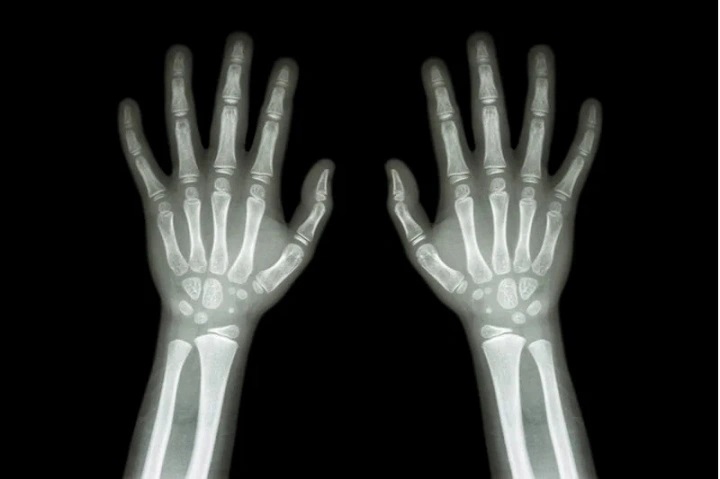

- X-ray showing plates have joined together

Doctors verify the closure of growth plates by looking at an X-ray of the pelvis, knee, or wrist.

A doctor’s X-ray is the only way to tell. A wrist or knee X-ray will show if plates are still open. Doctors may order a bone age study to evaluate both the chronological and biological ages.